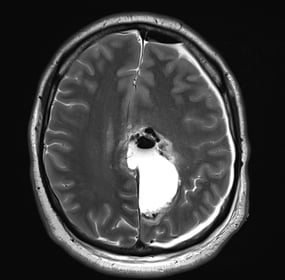

RMN postoperator: rezecție cvasicompletă confirmată imagistic